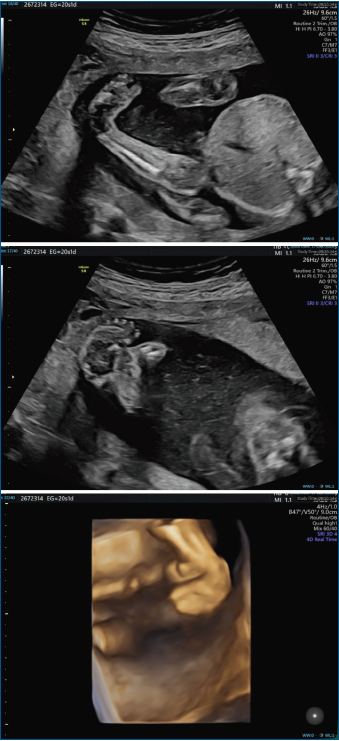

El pie zambo se puede detectar por ecografía a partir de la semana 12 de gestación (Figura 1). Los primeros informes de imágenes prenatales del pie zambo mediante ultrasonido aparecieron en 1985(8). Desde entonces, la detección del pie zambo mediante ecografía ha mejorado drásticamente en las últimas dos décadas, aunque los diagnósticos falsos positivos siguen siendo elevados, con valores que oscilan entre el 10 y el 40%(8,9,10).

El diagnostico diferencial principal es entre el pie zambo verdadero, categorizado como una anomalía estructural del pie resultante de una malformación en el desarrollo, y las deformidades posicionales del pie debido a la restricción intrauterina que afecta a un pie normal, como el pie supinado y el metatarso varo.

Brasseur et al. describen un análisis sistemático del pie fetal en 3 planos. En el corte sagital de la pierna, incluyendo la tibia, cuando hay posición constante del pie en flexión plantar (equino), lo más probable es que se trate de un pie zambo. Si es normal, podría descartar el diagnóstico de pie zambo. Si el corte sagital es normal y uno de los otros cortes no lo es, lo más probable es que se trate de una deformidad posicional del pie. Si el corte coronal es el único corte anormal y muestra supinación del pie, sugiere el diagnóstico de pie supinado. Si el corte transversal es el único corte anormal y muestra aducción del antepié, sugiere el diagnóstico de metatarso aducto(10).

Es importante tener en cuenta que la gravedad del pie zambo no se puede determinar mediante un examen ecográfico. Solo se puede determinar mediante un examen clínico del pie.

El diagnóstico prenatal ayuda a los padres a comprender la patología antes del nacimiento, lo que contribuye a fortalecer el vínculo entre padres e hijos, y les brinda tiempo para familiarizarse con el tratamiento y elegir el centro donde se va a realizar(8,9). Los estudios muestran que la mayoría de las madres prefieren informarse sobre el pie zambo antes del parto(8).